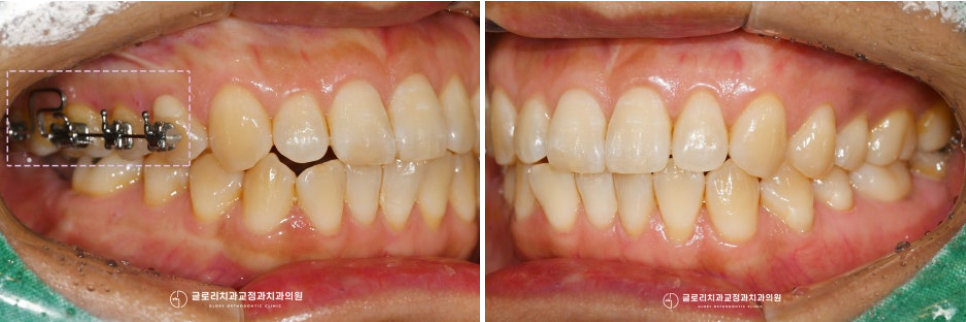

『3. 시행 완료』

중화동 치과 에서 진행한 어금니 부분교정은

10개월이 소요되었습니다.

아무래도 정출이 어느 정도 잡힌 뒤에

implant 보철 과정을 들어가야 됐기 때문에

하방으로 쭉 내려와 있던 27번도

함입으로 개선해 속으로 잘 들어간 모습인데요.

또한 구개면에 식립해두었던 미니 스크류도

안전하게 제거하여 이제는

편하게 생활하실 수 있으실 겁니다^^

새로 맞춰진 배열에 대합 되는

크라운 제작까지 완료되어

오른쪽으로 편하게 식사할 수 있어

마음에 드신다 하셨는데요.

치료 기간: 23.11~24.09